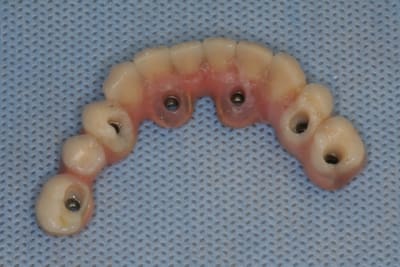

MCI bi-maxillaire, les guides chirurgicaux

vue d'ensemble du dispositif

bon, et bien c'est fait!

comme promis, et avec la bénédiction de posit, voici quelques morceaux choisis de cette journée...

ah, oui, j'allais oublier au maxillaire 8 legacy3 diamètre 3.7mm et en 13 de long (sauf 22 en 11.5mm)

mandibule 6 implants de 13mm et 3.7mm de diamètres (sauf 36 et 45 en 4.2mm/13)